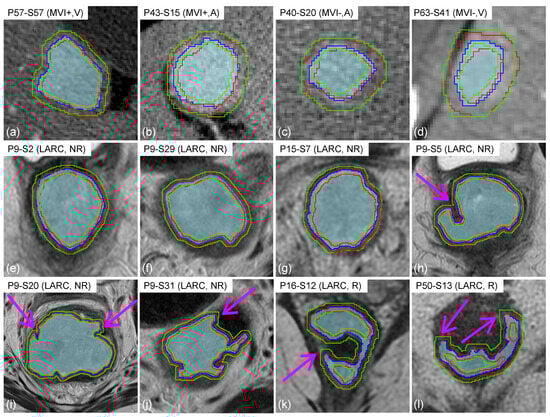

Figure 4 reports a panel of tRIM and ZoT ROIs for a few representative slices of the HCC-CT and LARC-MRI datasets.

The tRIM area is located between the two green lines, whilst the ZoT is the area located between the two red lines. As for the tumour core, it is bounded by the blue line and highlighted by a shade of blue. From a to d, Figure 4 shows a few slices of MVI+ (a,b) and MVI− (c,d) nodules both in the arterial (b,c) and venous (a,d) phases. Similarly, Figure 4e–l shows a few LARC slices, both in cases where ROIs have quite regular shapes and large sizes (e–g) and in cases where ROIs have irregular borders (h–l). In addition, the pink arrows in Figure 4h–l point out the key differences between the tRIM and ZoT ROIs, highlighting the most irregular parts of tumour edges.

Figure 4. Examples of the ZoT (in red), tRIM (in green), and tumour (the shaded area bounded by the blue line) ROIs. For each image, the patient identification code ( P x ) and slice number ( S y ) are indicated, along with the dataset the samples belong to (i.e., HCC or LARC) and their membership class (MVI+ or MVI− for the HCC dataset; R or NR for the LARC dataset). In addition, the pink arrows highlight the key differences between the tRIM and ZoT ROIs.

The analysis of peritumour has been acknowledged as being of a wide importance to obtaining useful information regarding the transition between inflammatory and cancer tissue. So far, the detection of the peritumour area has relied upon two main alternative approaches: (i) when applicable, the manual segmentation of the peritumour based on tumour appearance; and (ii) the dilation of the binary tumour segmentation mask using a prefixed size, disregarding the information retained by the underlying GL images. In this study, we present the first adaptive method based on image contrast variations to automatically detect the ZoT boundaries, conceived to work with different tumour tissues and scanning technologies. The performance of the method was assessed on a CT and an MRI dataset, the HCC and LARC, respectively, showing a markedly different radiological appearance. Indeed, while HCCs are nearly circular small nodules with shaded borders, LARCs have a larger size, with a well-defined anisotropic, jagged shape. Hence, in cases where nodules have a regular, nearly circular shape (Figure 4a–g), the ZoT adaptive detection appeared highly similar to that of tRIM, with intersecting edges often overlapping. Nevertheless, despite their similarity, being anisotropic, the ZoT ROIs included uneven portions of the peritumour area. This led to some ZoT margins overlapping the tumour ones. For instance, in Figure 4e, the ZoT includes more peritumour in the lower and the right sides than in the upper and the left ones, which was caused by a variability in the local image contrast. The same phenomenon appears in Figure 4f,g. On the other hand, in the presence of small concavities (Figure 4h–l), tRIM shows its weakness, since its underlying morphological operations cannot follow the anatomical profiles, as emphasized by the straight lines, and, even worse, it may include adjacent structures of a different nature that could yield misleading features.